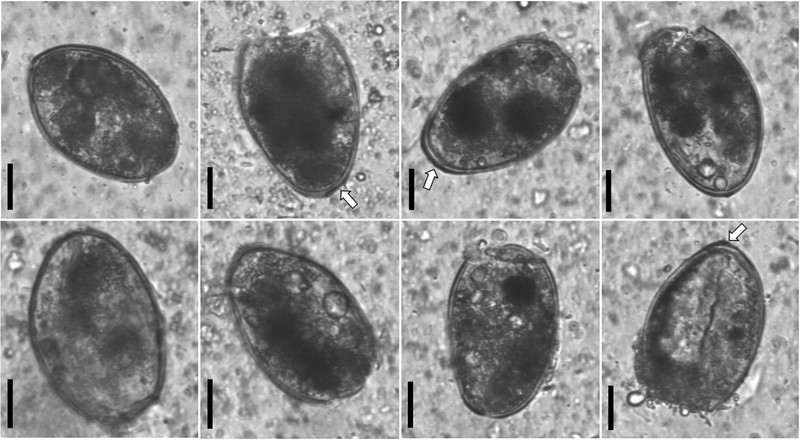

Компьютерная томография обнаружила в печени 375-летней мумии мужчины странное образование. Детальный анализ показал, что в тканях присутствуют яйца трематод вида Paragonimus westermani - паразитических плоских червей.